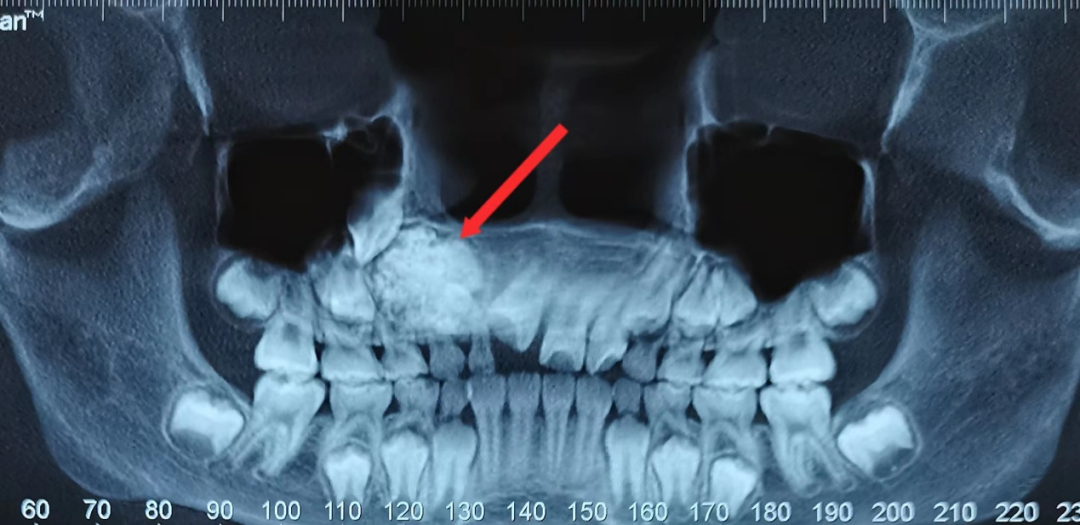

▲曲面断层片示:右上颌骨内大小不等、形态各异的牙体堆积高密度团块影

患者为一名8岁小女孩,因牙齿不齐、门牙迟迟不换,在外院检查发现右侧上颌骨内有一肿物,考虑为“组合性牙瘤可能”,来院就诊。影像资料显示,小孩子右上颌骨内有大小不等、形态各异的牙体堆积高密度团块影。